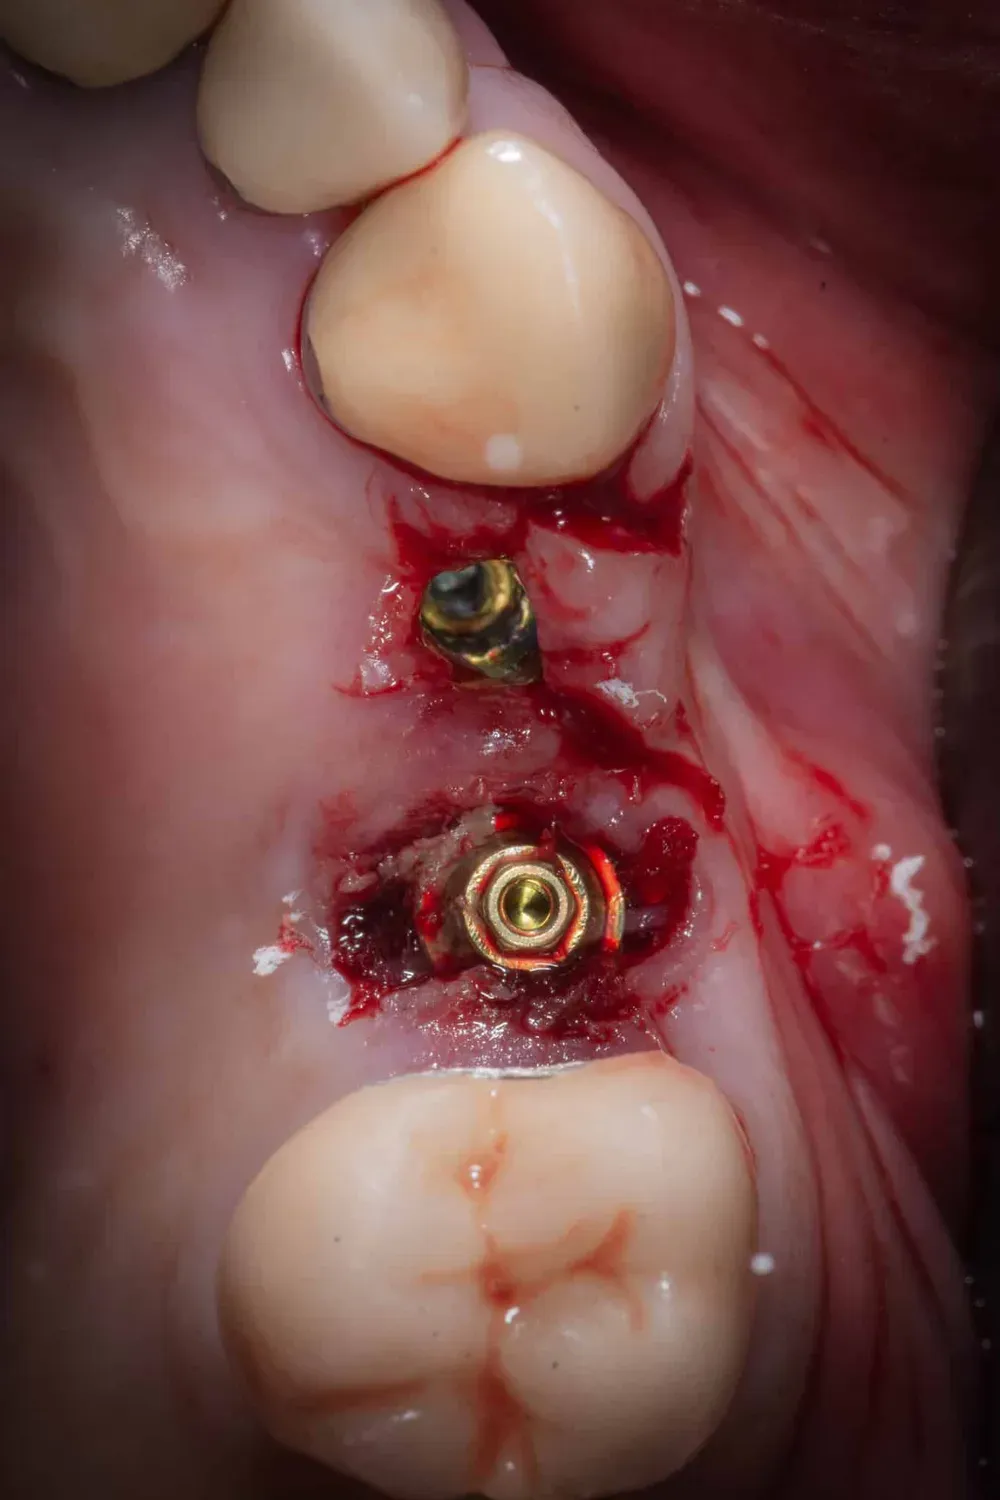

La Finalizzazione con Provvisorio a Carico Immediato

La foto che segue mostra gli impianti in posizione prima della connessione dei monconi protesici (sempre conici). La stabilità di entrambi era superiore ai 50Ncm.

Immagine occlusale immediatamente dopo l

Immagine occlusale immediatamente dopo l’inserimento degli impianti